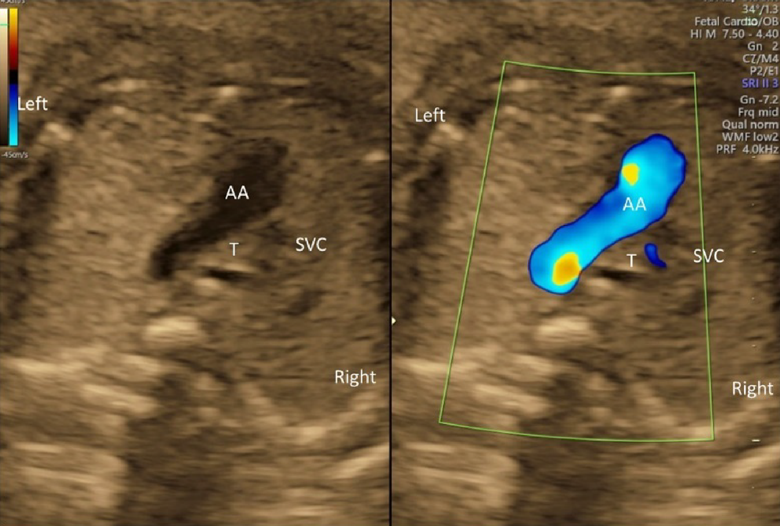

(5) Three-Vessel Trachea View

The 3VTV is obtained by translocating the probe parallelly from the 3VV plane to the cranial aspect of the fetus (Fig. 12). The superior vena cava, the trachea, the aortic arch, and the ductal arch are observed; in this order from the right to the left. The left aortic arch normally runs along the left side of the trachea, and the aortic arch and the ductal arch merge together on the dorsal side, forming a V-shape there. Either the aortic arch or the ductus arteriosus has anterograde blood flow. Some abnormalities can be recognized in the 3VTV.

1. Significant Differences in Diameters of the Aortic Arch and the Ductal Arch

Diameters of the aortic arch and the ductal arch are typically similar. When the aortic arch is narrow, aortic coarctation or interrupted aortic arch should be suspected.

2. Absence of a Unilateral Arterial Arch

In fetuses with pulmonary atresia without central pulmonary arteries or in those with persistent truncus arteriosus, the ductal arch is not found in its normal position. Only the aortic arch is to be seen. When the aortic arch is interrupted, in contrast, the ductal arch forms a solitary arch without connection to the ascending aorta. In fetuses with transposition of the great arteries, both arterial arches are present with the ascending aorta in front of the pulmonary trunk. The V-shaped connection is, therefore, not shown in a single horizontal plane, but a long aorta appears in the antero-posterior view (I-shaped sign).56)

3. Abnormal Direction of Blood Flow across the Arterial Arches

Blood flow across the ductal arch is retrograde in fetuses with stenotic lesions of the right heart, such as pulmonary atresia. Blood flow through the aortic arch is retrograde in fetuses with obstruction of the left heart, such as hypoplastic left heart syndrome. Premature constriction of the ductus arteriosus is to be suspected when the ductus arteriosus blood flow cannot be seen in the normal range of velocity or when the distal end of the ductus arteriosus is not connected to the aortic arch, irrespective of the size of the ductus arteriosus.

4. The Aortic Arch along the Right Side of the Trachea

When the aortic arch is found along the right side of the trachea with the ductal arch found on the the left of the trachea, it is likely vascular ring. Without detecting the left-sided arch structure, it is probably a solitary and right-sided aortic arch.